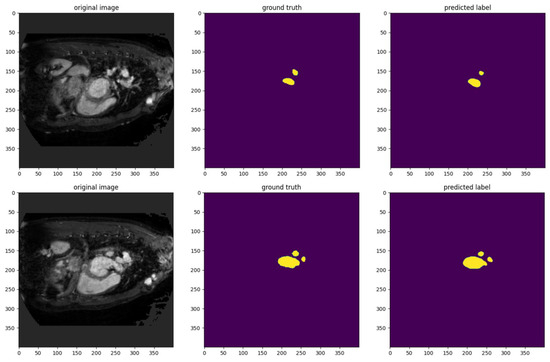

This study also performed qualitative analysis to evaluate the performance of our model against ground truth annotations. Figure 8 shows the model’s segmentation performance on sample images. Our model demonstrates a high degree of accuracy in replicating the ground truth segmentation, as the predicted labels closely align with the annotated regions. The mask regions in the predicted labels capture the shapes, sizes, and locations of the target areas in the ground truth. This indicates that the model effectively identifies and delineates the areas of interest.

Figure 8.

The visualization results of AMU-net to evaluate the performance of the model.